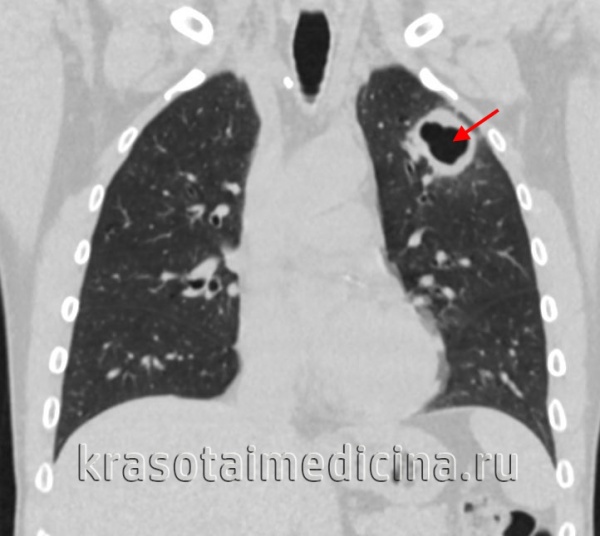

- Рентгеносемиотика диссеминированного туберкулеза легких зависит от клинической формы заболевания. Признаками острого процесса служат наличие в обоих легочных полях множественных однотипных очагов, расположенных симметрично, в виде цепочки по ходу сосудов. При подострой диссеминации очаги имеют тенденцию к слиянию, возможно образование полостей распада. Для хронической диссеминации характерно асимметричное расположение очаговых теней, которые имеют разную форму, величину, очертания, интенсивность в зависимости от срока давности их возникновения. Рентгенография легких, как правило, дополняется линейной или компьютерной томографией.

КТ ОГК. Множественные очаговые поражения верхней и средней доли правого легкого, верхней и нижней доли левого легкого у пациента с диссеминированным туберкулезом.